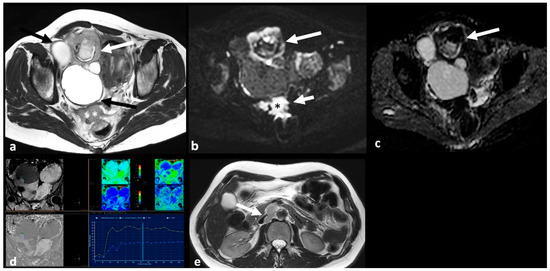

2.3.4. Lymphoma